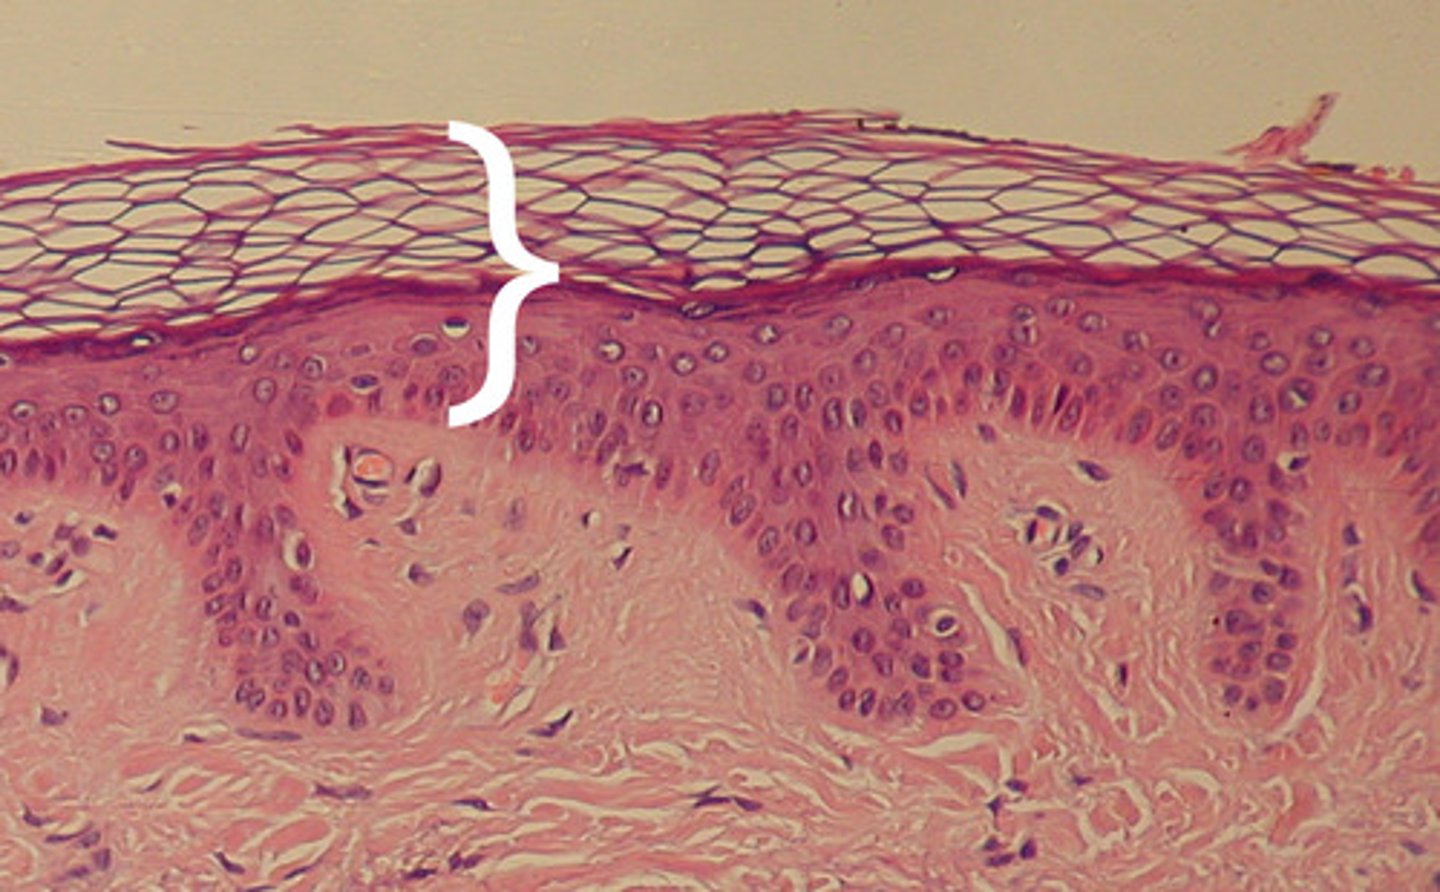

Stratum Corneum

the most superficial layer of the epidermis consisting of dead cells (flattened keratinocytes with no nuclei)

function: protection for epidermic, physical insults/water loss

basement membrane

- dense protein layer

- hemidesmosomes connect s. basal to BM

- function: physical barrier, connects epidermis -> dermis